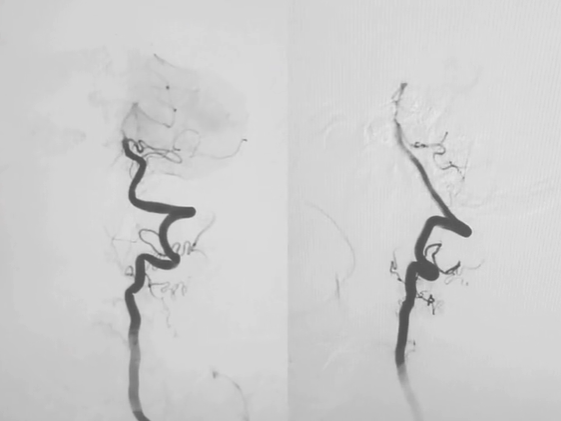

造影定位,锁定病变:

wuwei

左侧锁骨下动脉盗血

锁骨下动脉重度狭窄